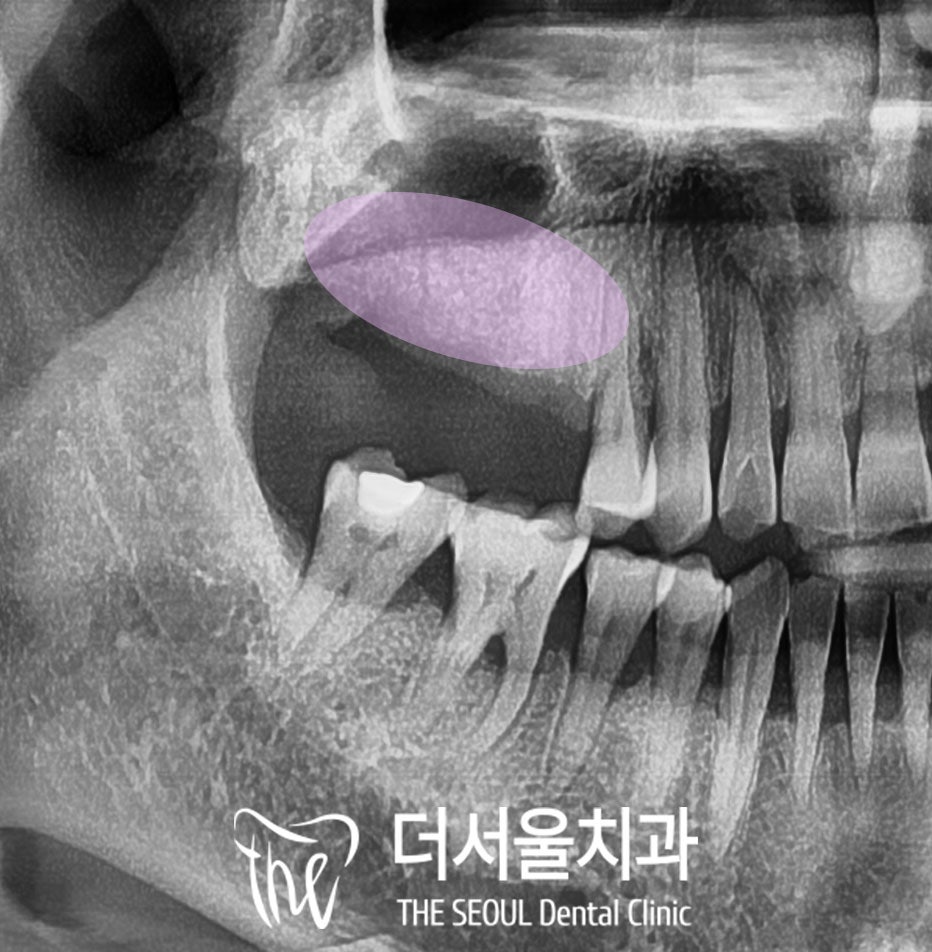

3. 디지털 네비게이션 가이드

이 케이스에서 수술할 부위는

앞서 말씀드린 것처럼

상악동이 있는 어금니 위턱뼈입니다.

그래서 수진동 임플란트 시술 전

디지털 방식을 이용하여

남은 잔존골의 양이 부족하다 보니

이대로는 픽스처를 심을

충분한 길이가 확보되지 않아

상악동을 들어 올리는 거상술을

동시에 진행하기로 했습니다.

또한 얇고 좁아진 잇몸뼈에서

어디에 심어야 픽스처가 제일 잘

고정될 수 있을까 고민하며

사전 식립을 진행해 보았습니다.

나중에 올라갈 크라운의 형태까지

계획하여 픽스처 간의 거리

기울기도 결정해 줍니다.